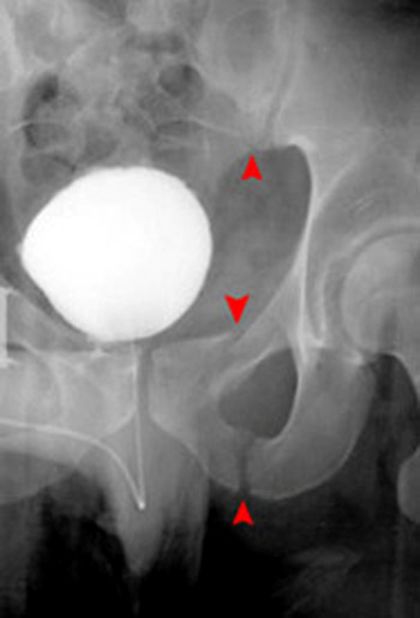

髋关节前脱位

疼痛科怎么理疗疼痛科医生、康复理疗科医生、针刀针灸医生应掌握的常见骨科疾病X光片_https://www.jmylbn.com_新闻资讯_第49张